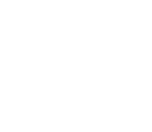

- 과잉치제거

- 까다로운 매복 과잉치 발치, 임플란트와 동시에 가능할까?

- 과잉치제거

- 까다로운 매복 과잉치 발치, 임플란트와 동시에 가능할까?